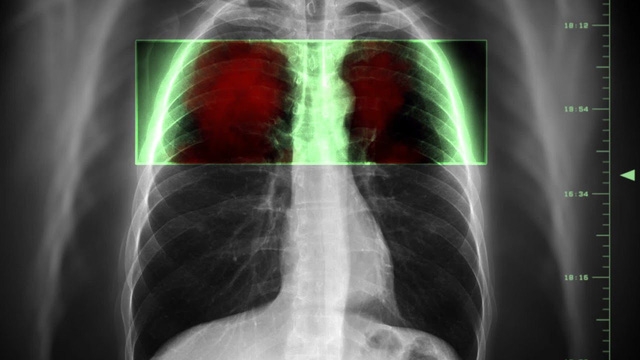

Trung tâm kiểm soát và phòng tránh dịch bệnh Mỹ (CDC) đã công bố phát hiện "đột phá" trong quá trình điều tra nguyên nhân gây ra v ở những người hút thuốc lá điện tử.

Theo đó, vitamin E khi dùng ở dạng viên uống hay bôi trên da thì an toàn, song khi hít vào ở dạng giọt nhỏ có dầu lại trở nên nguy hiểm chết người. CDC đã xác định chất vitamin E acetate dường như là nguyên nhân dẫn tới hàng chục trường hợp mắc bệnh phổi ở những người hút thuốc lá điện tử, sau khi tìm thấy chất này trong mẫu bệnh phẩm của 29 người mắc bệnh phổi được chọn ngẫu nhiên.Theo báo Guardian (Anh), đây được cho là phát hiện đột phá và đáng kể nhất trong quá trình điều tra nguyên nhân gây các bệnh về phổi của hơn 2.000 người bệnh có liên quan tới thuốc lá điện tử thời gian qua ở Mỹ. Việc phát hiện vitamin E acetate trong các mẫu bệnh phổi là chứng cứ đầu tiên cho thấy mối liên quan trực tiếp giữa chất này và các tổn thương về phổi ở người hút thuốc lá điện tử.

Trước đó, các nhà điều tra hé lộ khả năng tinh dầu acetate là nguyên nhân dẫn tới loạt trường hợp mắc bệnh phổi ở những người hút thuốc lá điện tử. Tinh dầu này được sử dụng như chất làm đặc trong tinh dầu thuốc lá điện tử có chứa hợp chất THC (tetrahydrocannabinol), một thành phần có trong cây gai dầu.Mặc dù vitamin E acetate được tìm thấy trong tất cả 29 mẫu bệnh phẩm của người bệnh ở nhiều bang khác nhau, song bà Anne Schuchet, phó giám đốc phụ trách CDC, thận trọng cho rằng cần có thêm những nghiên cứu khác để chính thức xác nhận chất này là nguyên nhân gây bệnh.Vitamin E đã được dùng là chất làm đặc trong dung dịch thuốc lá điện tử, nhất là trong một số sản phẩm bán ở chợ đen. Chất này được dùng để pha trộn vào các loại thuốc lá điện tử có chứa THC, thành phần trong cần sa gây ảo giác cho người dùng. Trong các phân tích của CDC, người ta đã phát hiện THC có trong 23/28 mẫu bệnh phẩm, trong đó có 3 người bệnh nói không sử dụng các sản phẩm chứa THC. Phát hiện nicotine trong 16/26 mẫu bệnh phẩm.

Cùng lúc đó, các nhà nghiên cứu Canada đã xác định một loại tổn thương phổi mới liên quan tới thuốc lá điện tử, cụ thể là các loại hương liệu trong những điếu thuốc lá điện tử hình bút (vape pen) thông thường. Tổn thương này có triệu chứng giống với loại tổn thương "popcorn lung" (viêm tiểu phế quản tắc nghẽn) thường thấy ở các công nhân hít nhiều hương liệu từ các máy làm bỏng ngô.

Công bố mới được cho là càng đào sâu thêm những bí ẩn xung quanh thuốc lá điện tử, sản phẩm đang trở nên ngày càng thịnh hành. Nhóm nghiên cứu Canada cũng cho rằng thủ phạm là tinh dầu vitamin E sử dụng trong các sản phẩm thuốc lá điện tử, đặc biệt là những loại chứa hợp chất THC.

Các bác sĩ tại Trung tâm Khoa học sức khỏe London cho rằng ca bệnh trên chỉ ra một số chất hóa học, không chỉ riêng tinh dầu vitamin E, có trong các loại thuốc lá điện tử có thể gây tổn thương. Hiện đội nghiên cứu tập trung vào diacetyl vì chất này từng được chứng minh là gây ra những tổn thương tương tự. Bốn tháng sau khi ra viện, bệnh nhân vẫn có vấn đề về đường thở và các bác sĩ không dám chắc phổi của anh này có thể hồi phục hay không. Các trường hợp bị viêm tiểu phế quản tắc nghẽn thường là không thể hồi phục hoàn toàn.Tính tới ngày 7/11, CDC cho biết đã có hơn 2.000 trường hợp được xác định hoặc bị nghi mắc các tổn thương ở phổi liên quan đến hút thuốc lá điện tử, trong khi đó đã có 39 người tử vong do sản phẩm này.